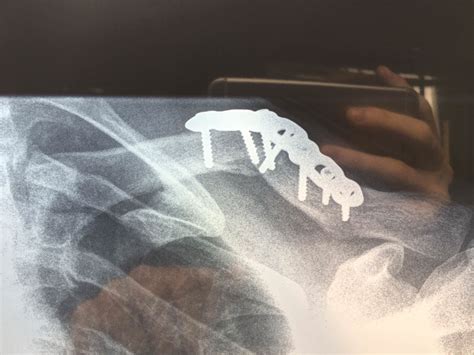

Clavicle | Definition, Anatomy, & Function | Britannica